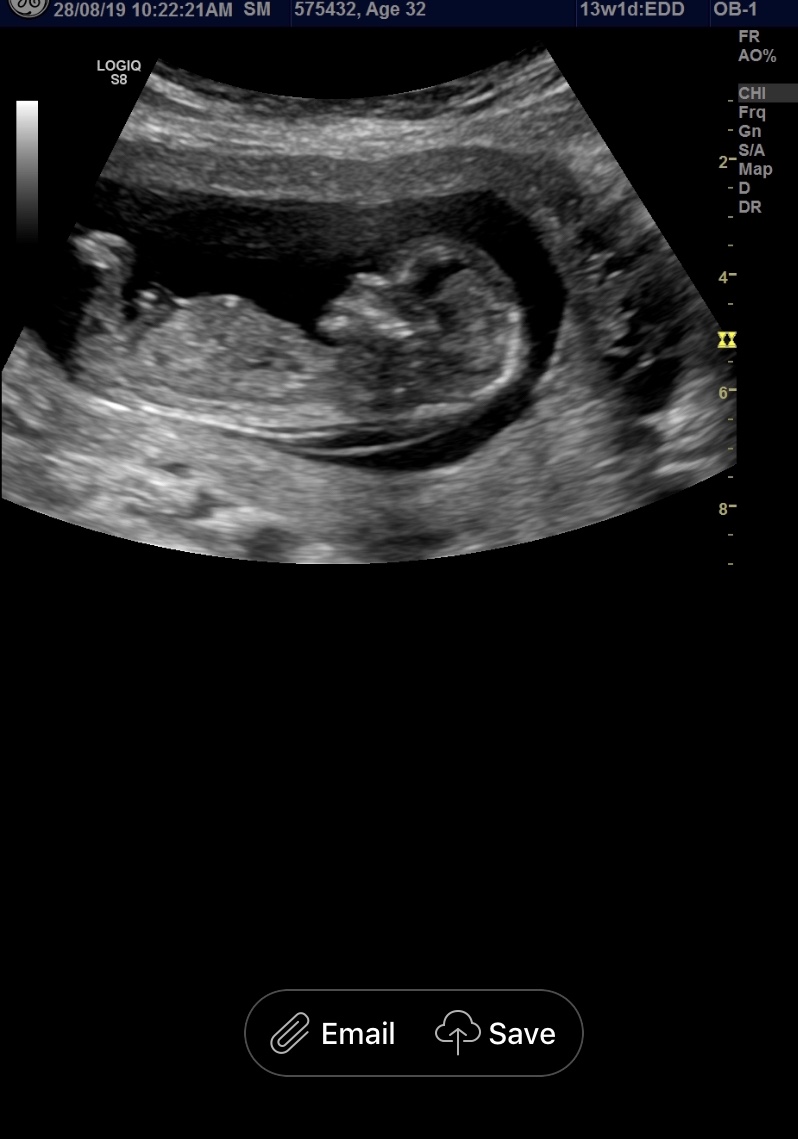

Hi Guy, would love it if you could tell me if my babe is a boy or girl. Thanks! Attachment 41923Attachment 41924Attachment 41925

Pink lean, but potty shots are not reliable for guessing at this point and that's not a clear nub.